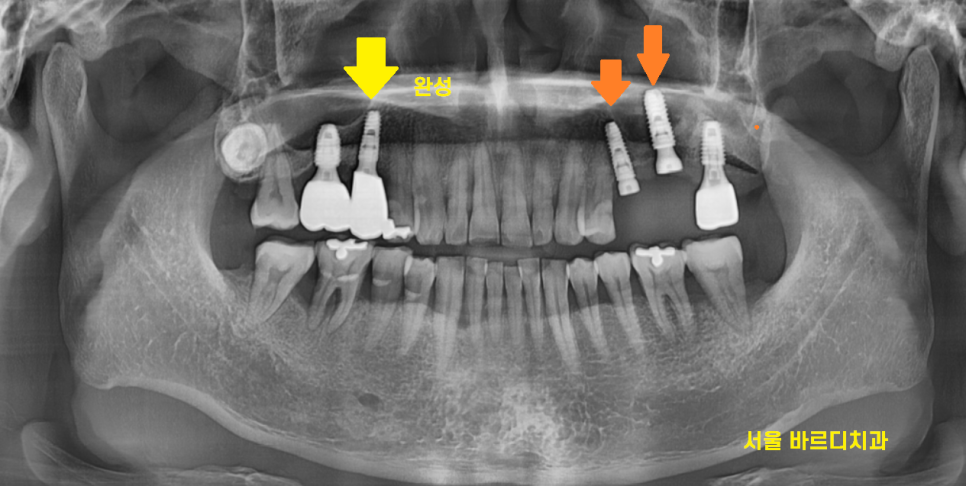

240622

왼쪽 치료가 끝나고

식사를 할 수 있게 된 뒤

오른쪽 치료를 시작했습니다.

잇몸 내려감으로 뼈 손실이 심하여

뼈이식을 진행하였는데요

240729

임플란트 완성한 모습입니다.

잇몸 내려감으로 뼈가 꺼져있었기에

회복에 집중했습니다.

부족한 부분은 뼈이식을 통해 보충

원상태로 복귀시켜드렸습니다.